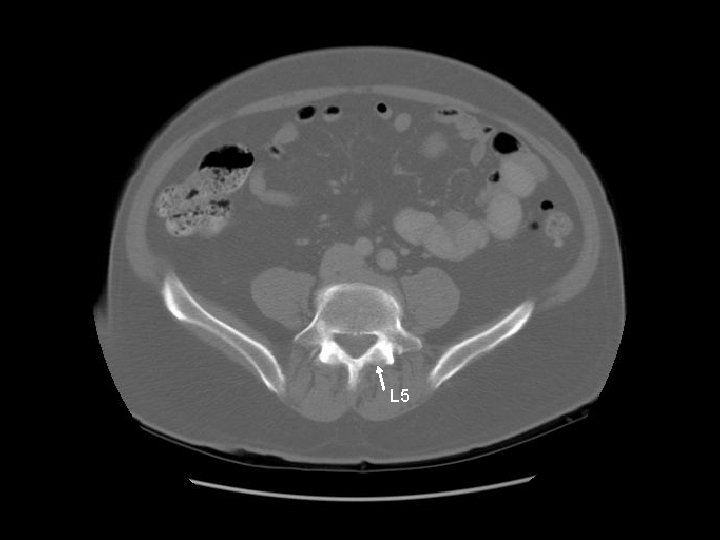

L 5

Arrows are pointing to the common iliac veins joining to form the IVC. Left